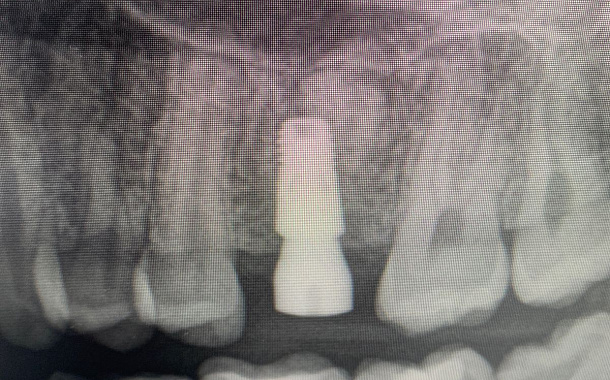

Применение Indiba после стоматологических процедур, таких как удаление зубов, костная пластика и имплантация, обеспечивает ряд значительных преимуществ:

- Улучшение приживаемости имплантатов: усиление кровоснабжения в области имплантации способствует лучшей интеграции имплантата с костной тканью.

- Исследование, опубликованное в Journal of Clinical Medicine (2020), показало, что применение Indiba после имплантации зубов ускоряет процесс остеоинтеграции на 30-40%.